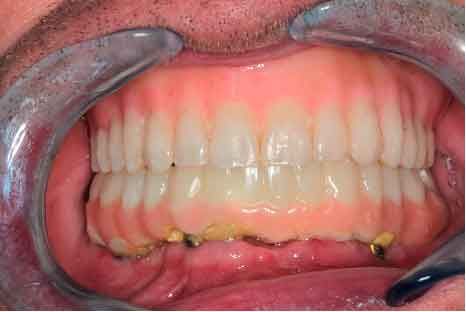

The periodontal structures of the remaining teeth are no longer sufficient. An edentulism is considered. The treatment plan is directed towards a removable maxillary complete prosthesis and an implant-supported mandibular complete prosthesis.

The challenge is to go from the initial situation to provisionals using patient data.

The dataset is sent to the lab to design the provisionals.

- Digital Workflow : Go from initial situation to provisionals using patient data, in a digital workflow